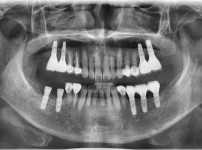

전체임플란트

임플란트